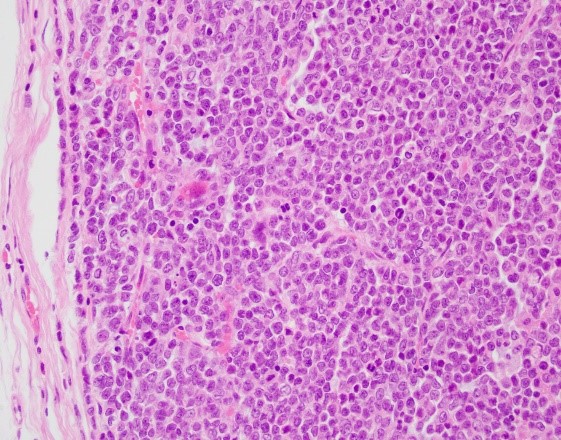

The sections show sheets of tumor cells in a background of marked necrosis. The tumor cells are small to intermediate in size, with scant cytoplasm, clump chromatin and small nucleoli. The tumor is positive for WT1, focally positive for CAM5.2, CD56, synaptophysin, negative for pan-cytokeratin, HMWCK, EMA, inhibin, OCT3/4, SALL4, CK7, CD10, chromogranin, SF1, and PAX8. P53 is wild type. CD45 highlights background lymphocytes. CD30 highlights scattered cells. P16 is non-contributory. SMARCA4/BRG1 staining shows absence of nuclear staining in the tumor cells (the nuclear stained stromal cells are used as internal control), supporting a diagnosis of small cell carcinoma of the ovary, hypercalcemic type.